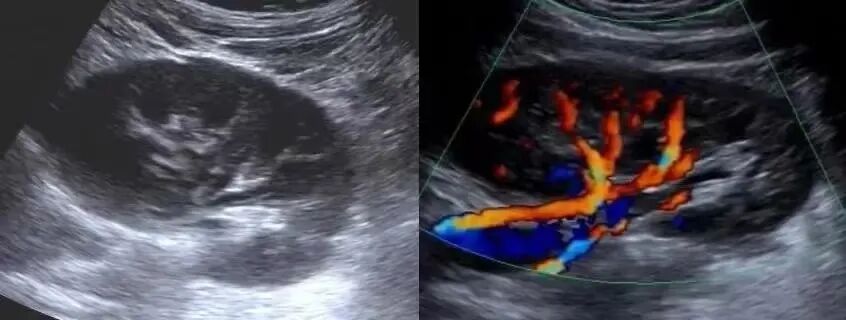

通常我们说的B超,全称为B型超声诊断仪,又称为黑白超声仪,以显示二维灰阶切面图像为主,是一种以亮度模式为诊断疾病的方式。彩超,全称为彩色多普勒超声显像仪,即在二维灰阶切面图像的基础上,叠加一幅彩色多普勒信号的二维图像,能直观显示血管形态、血流方向、流速和血流性质(层流或湍流),同时可采用脉冲多普勒和连续多普勒等功能。

左图为肾脏二维超声图像,右图为加上彩色多普勒功能图像,清晰显示肾血管分布。